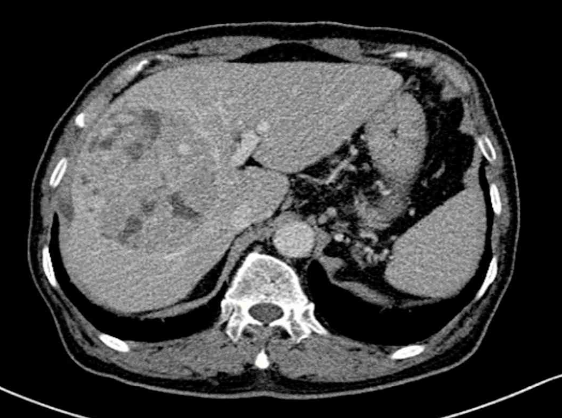

55세 남자가 1개월 전부터 오른쪽 윗배에서 덩이가 만져 진다고 병원에 왔다. 혈압 140/80 mmHg, 맥박 98회/분, 호흡 14회/분, 체온 36.9°C이다. 오른쪽 윗배에 압통이 있으며 반동압통은 없다. 혈액검사 결과는 다음과 같다. 복부 컴퓨터 단층촬영 사진이다. 진단은?

CT: Hepatic mass at right lobe, early enhancement-early washout

B형 간염 환자에게서 1cm 이상의 종괴가 확인되고, 조영증강 CT상 early enhancement-early washout 소견이 확인되었으므로 간세포암종으로 진단한다.

• 조영증강 CT상 간 우엽에서 large mass가 관찰되며, 동맥기에는 주변 조직에 비해 밝게 조영증강되었다가, 정맥기/문맥기에는 주변조직보다 어두워지는 early enhancement-early washout 소견이 확인된다.

B형 간염 환자에게서 1cm 이상의 종괴가 확인되고, 조영증강 CT상 early enhancemnet-early washout이 확인되었으므로 추가적인 조직검사 없이 간세포암종(hepatocellular carcinoma)로 진단 가능하다.

• 본 증례의 첫 번째 사진은 aorta가 밝으므로 동맥기이고, 두 번째 사진은 portal vein과 aorta의 밝기가 비슷하므로 문맥/정맥기이다.